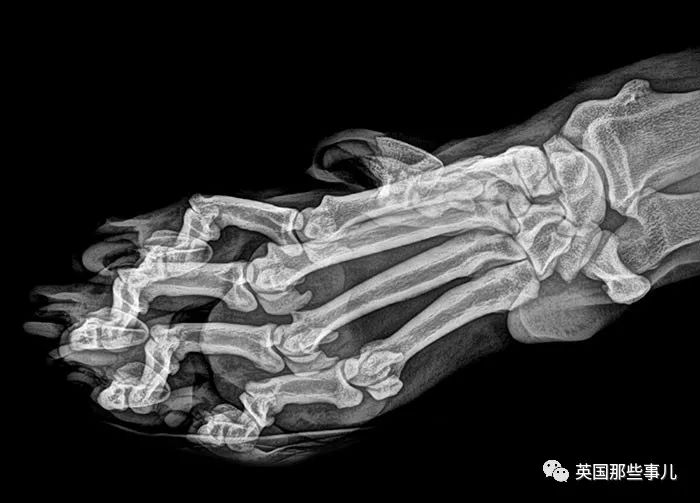

穿著恨天高的jio

哎呀,看著就很糟糕....